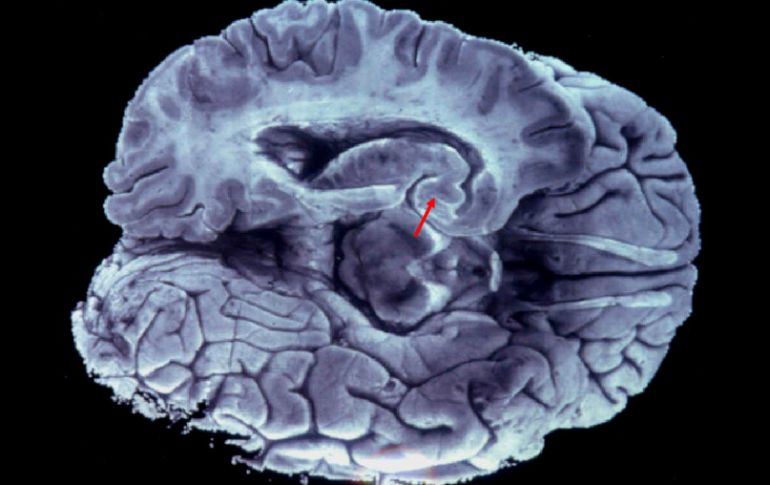

Tecnología | Científicos hallaron que determinadas células computan la longitud del sonido Descubren cómo el cerebro detecta los sonidos cortos Científicos hallaron que determinadas células computan la longitud del sonido Por: EFE 14 de marzo de 2016 - 20:41 hs Cuando el proceso de las células del cerebro no funciona, puede dificultarse el reconocimiento de palabras. EFE / ARCHIVO WASHINGTON, ESTADOS UNIDOS (14/MAR/2016).- Un grupo de científicos ha descubierto cómo determinadas células del cerebro computan la longitud del sonido y detectan los sonidos cortos, según un estudio publicado hoy en la revista Proceedings of the National Academy of Sciences. Hasta ahora, se sabía que diferentes células nerviosas (neuronas) responden selectivamente a sonidos de cierta duración, pero no se conocía cómo esas células computan la longitud de los sonidos. Esta nueva investigación, elaborada mediante el estudio de ranas, revela cómo una célula cerebral responde a un sonido corto: se inhibe mientras dura el sonido y se excita después para lanzar la señal nerviosa. En sonidos largos, la célula se inhibe durante un periodo más largo, lo que contrarresta la excitación, de manera que la célula no responde a este tipo de sonidos. "Esta integración de la excitación y la inhibición en el cerebro es un componente crítico de la capacidad para distinguir entre los sonidos de la comunicación", explica Gary Rose, investigador principal del estudio y profesor de biología en la Universidad de Utah (EU). Cuando ese proceso no funciona, puede haber dificultades para el reconocimiento de palabras, como en el caso de las personas mayores que experimentan ese problema incluso usando audífonos que amplifican los sonidos. "Se cree que el deterioro en el reconocimiento de palabras es, en buena medida, una consecuencia de los desequilibros en la excitación e inhibición de las neuronas involucradas en la audición", señala Rose. Distinguir entre sonidos cortos y largos es imprescindible tanto en los humanos, para entenderse al hablar, como para la comunicación entre animales. Este estudio ha sido elaborado por científicos de la Universidad de Utah con financiación del Instituto Nacional de la Sordera y Otros Trastornos Comunicativos de Estados Unidos. Temas Estudios científicos Ciencia médica Cerebro Lee También Julieta Fierro será homenajeada en la FIL INAPAM: ¿Cómo solicitar un turno para consulta médica gratuita? Nobel de Química premia el desarrollo de estructuras metal-orgánicas Nobel de Física para Clarke, Devoret y Martinis por descubrimiento sobre fenómenos cuánticos Recibe las últimas noticias en tu e-mail Todo lo que necesitas saber para comenzar tu día Registrarse implica aceptar los Términos y Condiciones